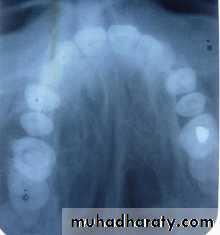

Position of canine root apex anteroposteriorly

Vertical canine crown height